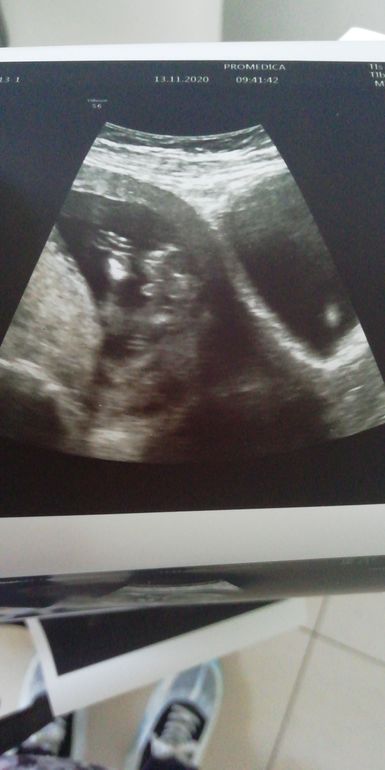

Кажется, мальчик ❤️

Да это мальчик

На таком сроке смотрят по наклону, а не в такой проекции, как у вас, так как половые органы выглядят одинаково, отличается только угол наклона

Wanderlust, по всякому смотрели. Про наклон врач тоже объяснила.

В общем вероятность ошибки очень высока. Может угадали, может нет, заранее настраиваться не стоит, от 16 нед уже точнее результат

Такое же фото есть, в 14 недель мальчика предположили, на следующих узи подтверждают 😊

Ks-ks, сверху и снизу ножки, между ними, соответсвенно, причинное место) Муж у меня тоже не разобрался, где там что, он вообще девочку ждал)) Тоже так хотела сначала, но любопытство взяло верх)